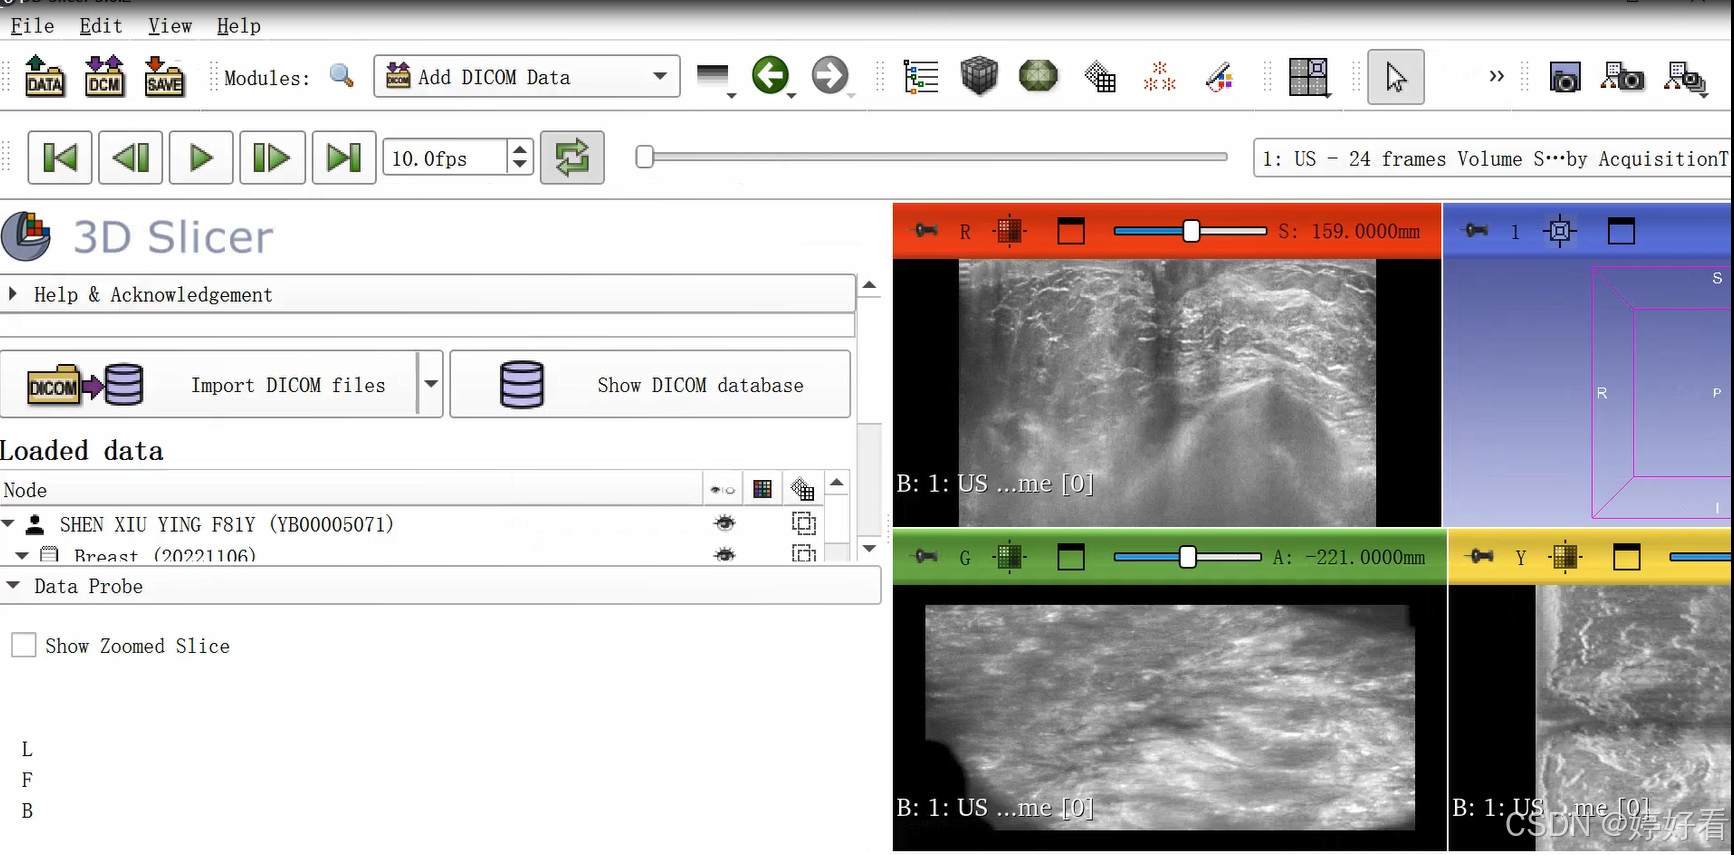

1、添加数据

1.1 首先,把包含DICOM格式影像图片的文件夹直接拖到3D slicer的界面,然后点击OK。

1.2 选中Patient name,然后依次点击Examine-Load,这样图片就打开了。